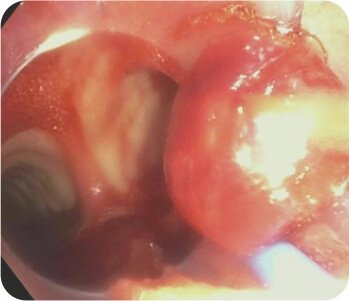

ডান উপরের লোবের অগ্রভাগের ওয়াটানাবে স্ফিগট অক্লুশন + ডান এপিকাল এবং পোস্টেরিয়র সাব সেগমেন্টের আঠালো ইনস্টিলেশন এবং ব্রঙ্কিয়াল আর্টারি এমবোলাইজেশন করা হয়েছিল।

ডান উপরের ব্রঙ্কাসে স্ফিগট বসানো

ডান উপরের লোব ব্রঙ্কাসে স্ফিগট বসানো

ডান উপরের লোব ব্রঙ্কাসে আঠালো স্থাপন